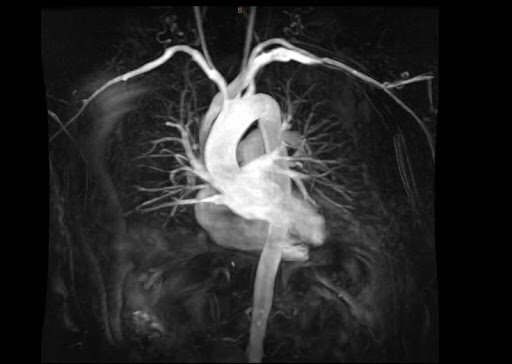

МРТ коронарных сосудов

МРТ коронарных сосудов сердца (она же КТ коронарография) - это обследование артерий и вен, которое входит как составная часть в комплексную МРТ сердца и коронарных артерий. В ходе данного сканирования детально оценивается сердечная сумка, сердечные мышцы, перикард и кровоснабжающая система. Поскольку данный орган грудной клетки находится в постоянном движении, его томографическое сканирование вызывает определенные сложность и требует современного аппарата и опытного рентгенолога. Для качественной МРТ коронарных сосудов сердца рекомендован сверхвысокопольный томограф мощностью 3 Тесла. Цена такого обследования не будет дешевой, однако информативная ценность сканирования и качество снимков будет максимально высокими. К стоимости МРТ артерий и вен сердца могут быть добавлены затраты на контрастирование, если заболевание пациента требует проведения МРТ коронарных сосудов и сердца с контрастом. Обычно такой протокол применяют при подозрениях на опухоли и онкологические патологии.